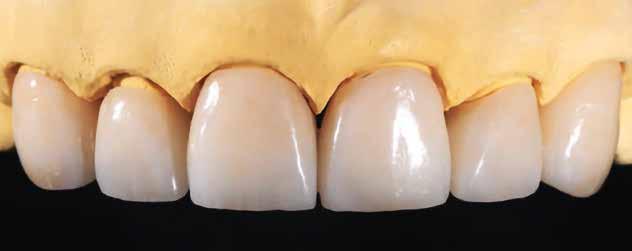

Tervezés és kivitelezés a laboratóriumban

Az implantátumról készült lenyomat, valamint az alginát antagonista fertőtlenítése után szuperkemény gipszből az előírások szerint elkészültek a minták. A felső mintát a technikai implantátum körül levehető ínymaszkkal készítettük. SAM-arcív segítségével habituális okklúzióba helyeztük a mintákat. A felső mintát előkészítettük a digitális tervezéshez, enyhén megformáltuk az emergenciaprofilt, hogy tökéletes legyen a rózsa-fehér esztétika. A fogszínt – a pácienssel történt egyeztetést követően – dokumentáltuk.

Digitális tervezés

A mintát beolvastuk (D1000, 3Shape), majd megterveztük a munkát (3Shape Dental System) (6. kép). A fel -